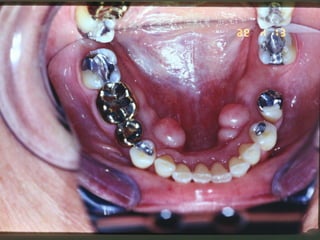

Aspectos ortologicos da mucosa bucal